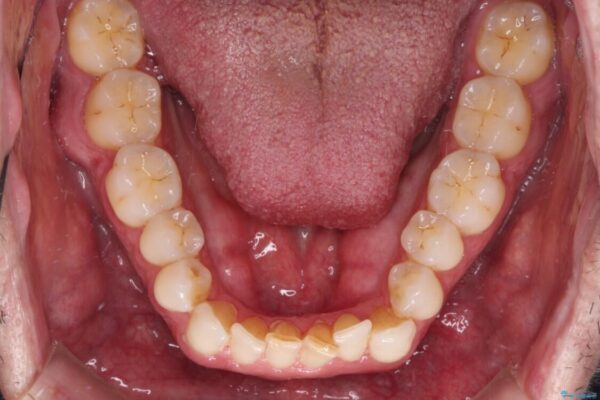

前歯でものを噛みきりたいとのことで来院された患者様です。

以前矯正治療を経験されたそうですが、舌の突出癖により上下前歯に隙間ができている様子でした。

治療前

• 前歯でものを噛みきりたい 目立たない装置でのワイヤー矯正 治療前画像